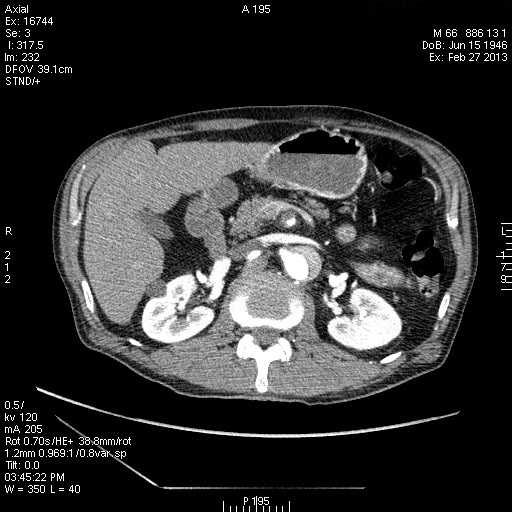

Расслаивающая аневризма аорты, Дебейки I

Пожилой пациент с жалобами на боли в грудной клетке. Болеет неделю.

Диссекция аорты 1 типа по DeBakey , Стенфорд А .